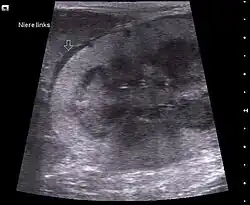

Maligne Lymphome der Niere machen etwa 15 % der Fälle aus und treten vor allem bei älteren Tieren auf. Die Blutwerte für Harnstoff und Kreatinin sind erhöht. In fortgeschrittenen Fällen kommt es zu einem Nierenversagen.